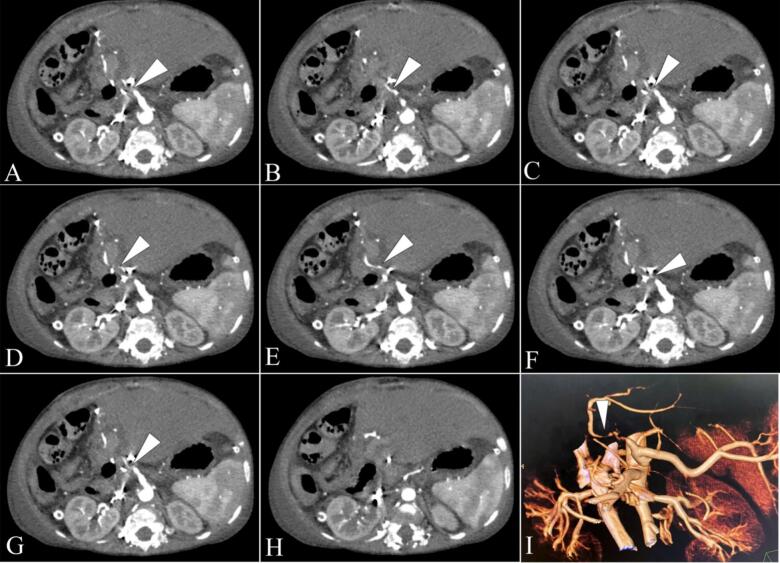

Presentation of case: A 13-month-old infant with biliary atresia post-Kasai procedure underwent living donor liver transplantation. On postoperative day 9, Doppler ultrasound detected signs of impending hepatic artery thrombosis, which was confirmed by computed tomography angiography. The patient was treated with intravenous alteplase at a dose of 0.3 mg/kg/h. After 3.5 hours of infusion, Doppler ultrasound showed improved hepatic artery flow. The infusion was stopped early due to intra-abdominal bleeding, which was managed conservatively. The patient stabilized without surgical intervention and was discharged on postoperative day 32 with stable hepatic artery flow. At six-month follow-up, the hepatic artery remained patent, and the patient was clinically stable.